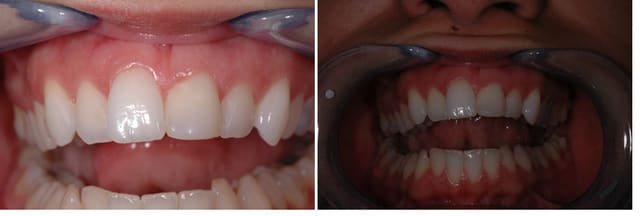

Patiente 21 ans, problèmes esthétiques liés à une 21 compositée et sur compositée suite à choc il y a dix ans.

Que comptes tu faire ? On aurait bien envie de mettre un petit coup de bistouri à la 21, mais jusqu'où ? (est-ce qu'il serait raisonnable de greffer la 11 pour faire un compromis ?).

Est-il possible de recréer un profil d'émergence plus apical avec une facette ?

J'adore les formes des dents de ta patiente, typiquement féminin, pas trop rond ni trop globuleux.

Un coup de bistouri et une facette semble appropriés mais que fais-tu de 23 si sa demande est d'ordre esthétique?

et la 11, elle a quoi? c'est du à la tof? elle me semble d'une teinte différente avec un état de surface plus brillant que le reste de la denture...

non justement, c'est un cas à résoudre. mais qui est résolvable simplement, comme je l'indiquais, par une gingivoplastie, et une facette.

donc première étape, ce sera la chir plastique, ensuite la facette.

1) La fracture dentaire est elle importante? Pourquoi pas un "simple" compo stratifié + gingivoplastie?

heureusement que tu as posé cette question Alain,car je croyais que le problème était sur la 11,vu sa hauteur ,sa couleur etc et le problème me semblait difficile à resoudre pour aligner son collet au niveau de celui de la 21

si c'est la 21 qui est en cause les solutions me paraissent plus faciles,plus aisé de soustraire que d'ajouter

oui. un bon tiers de la dent.

c'est le cas type d'indication de facette. il y a tout à corriger sur cette dent. non seulement la forme mais aussi la teinte. et ça la strat ne le permet pas sauf à faire une ... facette en composite. je préfère une facette céramique.

classique. choc pendant la croissance. donc évolution différente de cette dent, d'avec ses voisines.

moi je ne peux donner d'avis car sur cette photo c'est plutot la 11 qui choque plutot que la 21,même au niveau de la teinte

ce qui me gene en voyant ta patiente,c'est plutot la 11 trop vestibulee et les13 et 23

mais puisqu'on est dans la demande purement esthetique ,pourquoi ne lui proposes tu pas d'abord un alignement de 3-3(methode invisalign est tres bien pour ce cas),le resultat sera optimal